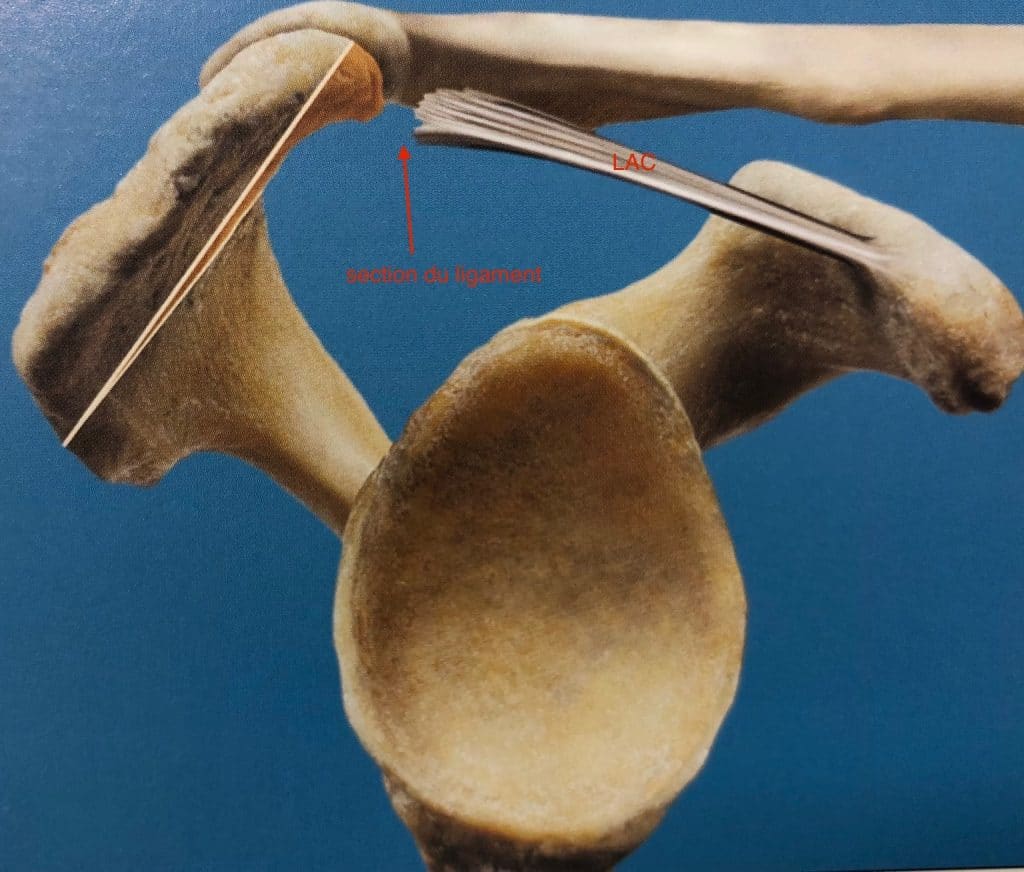

Acromioplastie

Section du ligament

La chirurgie

peut être envisagée en cas de persistance de la douleur et d’inefficacité de la rééducation. L’acromioplastie consiste à raboter l’os, sectionner le ligament et réaliser une bursectomie. En cas de calcification du tendon, elle sera supprimée en même temps.